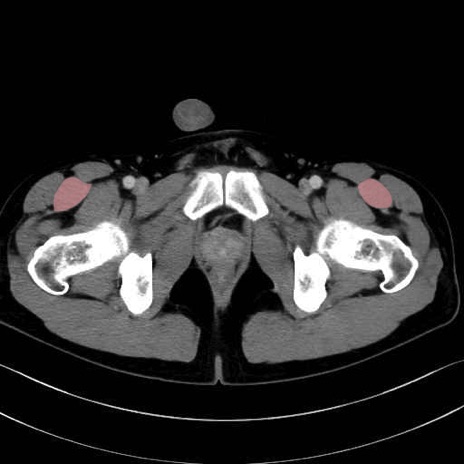

5. 大腿前面(大腿四頭筋群・伸筋群)

縫工筋 (Sartorius)

大腿直筋 (Rectus femoris)

外側広筋 (Vastus lateralis)

中間広筋 (Vastus intermedius)